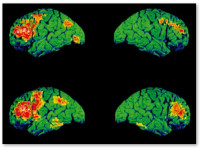

Исследование группы ученых из Университета Манчестера проливает новый свет на то, как употребление марихуаны влияет на шизофрению.   Согласно отчету, опубликованному в журнале Schizophrenia Bulletin 9 июля, ученые наблюдали за ...

Новое исследование, опубликованное в мае в журнале "Исследования шизофрении", пришло к выводу, что курение марихуаны не повышает риск развития психоза. Четырехлетнее наблюдение за 170 индивидами с высокой предрасположенностью к психозам показало, ...

Ученые из Гарвардского университета провели исследование, которое похоже опровергает распространенный миф о том, что курение конопли повышает риск развития шизофрении. Несколько предыдущих исследований обнаружили бóльшую распространенность шизофрении среди курильщиков марихуаны, чем ...